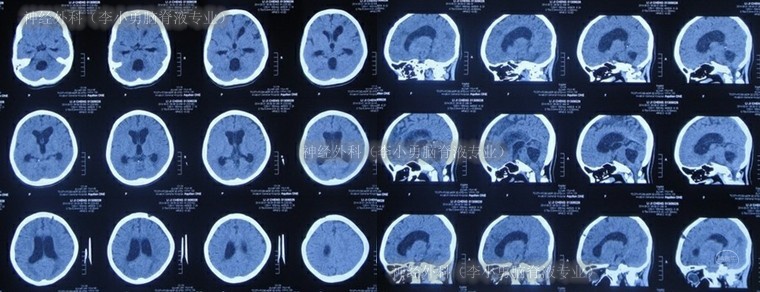

入院次日即2014年8月1日,查头颅CT(图-12)示脑室系统稍扩张(外院拔除脑室外引流后1天)。

图-12:2014年8月1日头颅CT

在术后第4天即2014年8月5日,查头颅CT示脑室较术前稍缩小(图-13)。

图-13:2014年8月5日头颅CT

住院21天即2014年8月20日,查头颅CT(图-14)后按计划进行了左侧侧脑室腹腔分流术。

图-14:2014年8月20日头颅CT

2014年8月28日(李小勇脑脊液专业治29天康复出院),出院时:神志清楚,精神状态好,言语流利,肢体活动正常(图-15);出院时头颅CT示无异常(图-16)。

图-16:出院时头颅CT